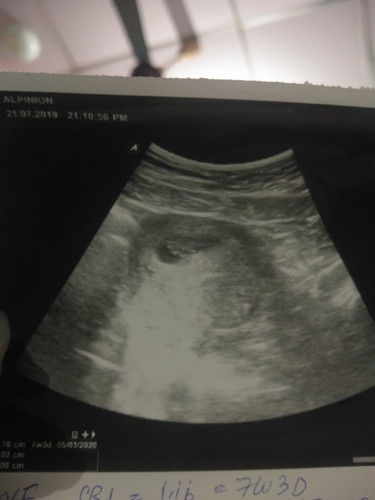

ไปซาวดูน้องมา..หมอบอกน้องได้7สัปดากับ3วันแล้วที่น่าตื่นเต้นไปฝ่านั้นคือ..คุนหมอบอกมีสิทได้ลูกแฝด

รบกวนคัยที่ดูใบซาวเปนช่วยดูทีค่ะ มีก้อนตัวเด็ก2อันแบบคุนหมอบอกหรือป่าว?